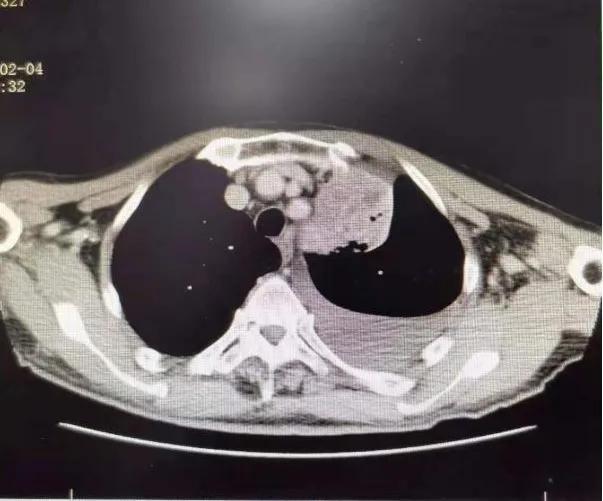

75岁的张爷爷患有慢性阻塞性肺疾病、脑栓塞等多种慢性病,体质较差,PS评分为3分,入院时有咳嗽咯血伴有气短乏力等症状,查胸部CT可见左上肺叶大小约8×4cm大小占位病变,纵隔淋巴结肿大,左侧大量胸腔积液。 气管镜可见左上支气管内新生物阻塞。 病理提示: 鳞状细胞癌。 诊断为: 肺癌(左肺 鳞癌 cT4N2M1a,IVA期)。 确诊后家属考虑患者年老体弱,合并多种疾病,拒绝放化疗,准备放弃治疗。

1个月后张爷爷来院复诊,复查胸部CT提示:左肺上叶肿块缩小到1cm,肺不张明显缓解,胸腔积液减少 。 张爷爷表示近1月来状态明显好转,未再咯血,活动也不像之前那样一动就喘,平时走路吃饭都不影响。入院后PS评分1分,临床疗效评估为PR。 为更好的控制肿瘤,进行了第二次介入治疗。 行支气管动脉及胸廓内动脉造影后显示肿瘤染色明显减少,继续灌注化疗药物后,将肿瘤滋养动脉进行了彻底栓塞。 术后无不适, 顺利完成第二次治疗。

第一次介入造影显示肿瘤供血动脉及肿瘤染色